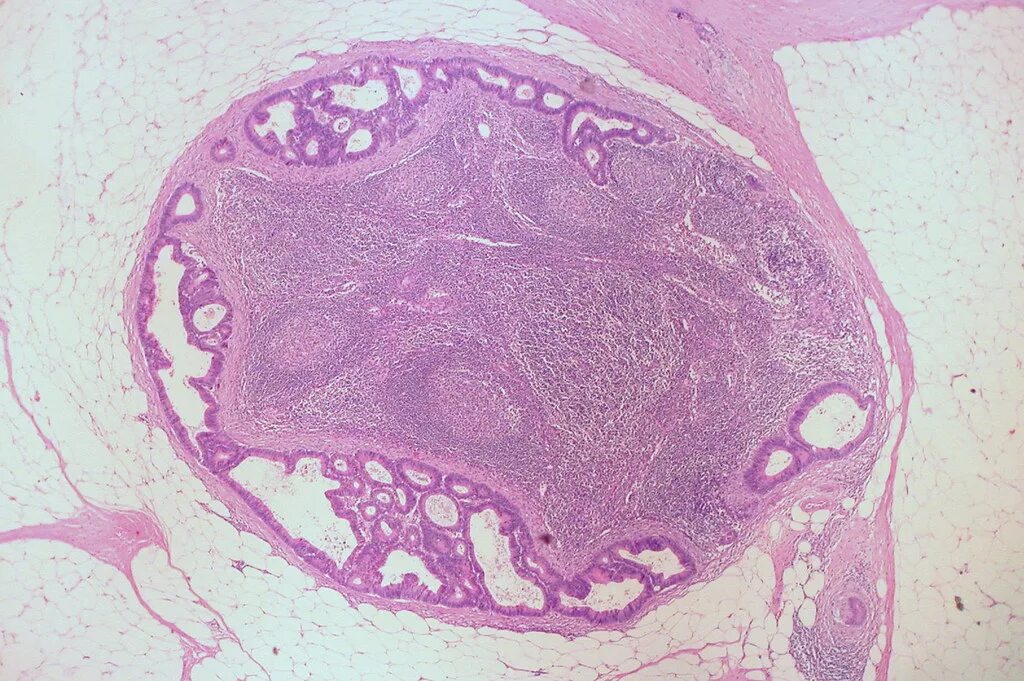

Метастазы в лимфоузлах легких